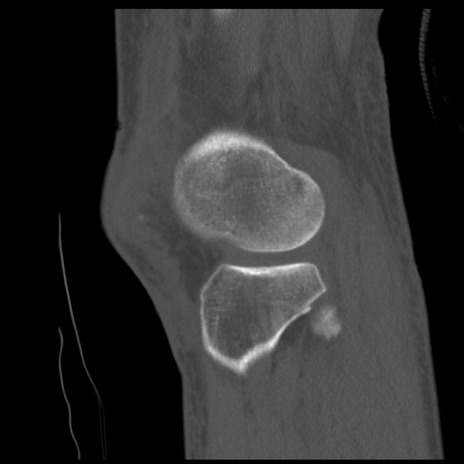

症例28 右膝関節CT(矢状断像)

右膝関節CT